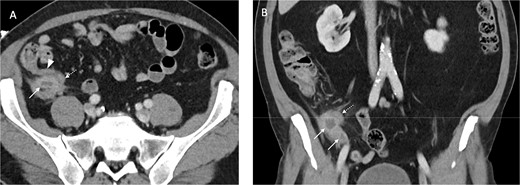

He was brought to theatre for a combined laparoscopic appendicectomy, drainage of peri-appendiceal abscess and cholecystectomy with intraoperative cholangiogram. Intraoperative findings included a 2 cm peri-appendiceal abscess cavity (Fig. 3) in keeping with pre-operative imaging. However, the gallbladder was gangrenous with a possible microperforation sealed by omentum (Fig. 4). Based on the intraoperative appearance, it was difficult to ascertain whether the abscess was due to primary appendicitis or whether the abscess was seeded from the cholecystitis and the appendix had become involved collaterally.

Final histology showed gangrenous cholecystitis with evidence of perforation and a calculus lodged in the gallbladder neck. Appendix histology showed features in keeping with a perforated diverticula at the tip of the appendix with associated active inflammation and no fecalith, suggesting that the two pathologies occurred independently of each other.